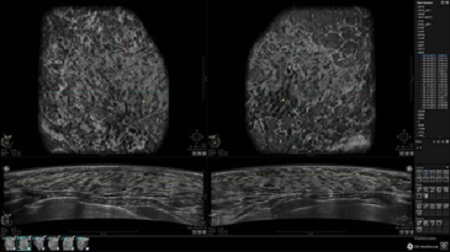

GE INVENIA ABUS – это современный УЗИ аппарат, который создан для точной и эффективной диагностики сканирования с высокой плотностью молочных желез. Выявляемость патологий раковых и предраковых стадий заболевания составляет 55%, что в конечном счете позволяет ставить врачу точные и своевременные диагнозы. Традиционные методы использования маммографии не показывают такой выявляемости, ограничиваясь лишь 3-38%.

УЗИ-аппарат GE INVENIA ABUS позволяет проводить максимально операторонезависимые процедуры, что значительно снижает риск неправильной постановки диагноза и сопутствующие издержки на обработку информации. Система готовит отчет в течение 3-х минут после сканирования, это безусловное преимущество по сравнению с обычным УЗИ сканером.

• Отображение объемных 3D ультразвуковых изображений, которые состоят из традиционных поперечных и воссозданных коронарных и сагиттальных проекций

• Многооконный просмотр: 4 - 12 изображений

• Стандартизованная ориентация изображения: «толстый срез» в коронарной плоскости; поперечная; сагиттальная плоскость; радиальный и антирадиальный поворот изображения; просмотр исключительно области интереса

• Одновременный просмотр двух изображений для сопоставления в коронарной плоскости